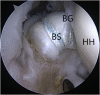

The long head of the biceps tendon (LHBT) is a frequent source of disorders and pathology in the shoulder. Significant evidence is available on the management of disorders of the LHBT in the literature, and the LHBT is frequently addressed intraoperatively when involved in shoulder pathology. An all-arthroscopic, intra-articular biceps tenodesis with suture anchor fixation has several advantages that have not been well described previously, and it does not add significant morbidity to arthroscopic surgery to treat the rotator cuff or other sources of pain. Intra-articular LHBT tenodesis in the bicipital groove thus has advantages of less surgical time and a decreased bone footprint.